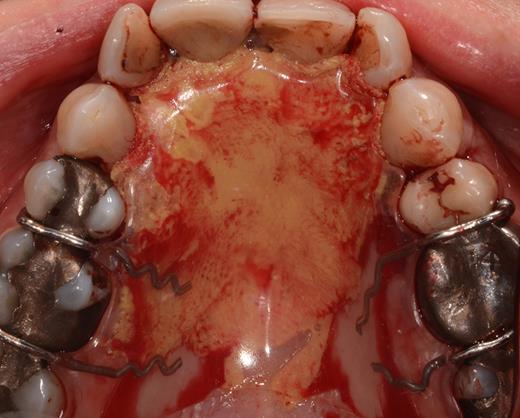

After a sulcular incision on the palatal side from teeth 15 to 25 and an incision in the midline of the palate omitting the incisive papilla and the two orifices of the NPD, two full-thickness mucoperiosteal flaps were raised. Thereafter, the incisive papilla and the whole contents of the incisive canal were enucleated (Figs 4–6). The bony incisive canal was filled with autologous bone harvested from the palatal region (bone scraper) (Fig. 7). A tension-free primary wound closure was achieved by moving the palatal flaps to the midline using single button and interdental vertical mattress sutures (Monocryl 4-0, Ethicon, Johnson & Johnson, USA) (Fig. 8). To avoid wound dehiscence and hematoma, an iodoforme gauze and a palatal plate were applied (Fig. 9). The patient was instructed to rinse three times a day with 0.1% chlorhexidine (formula hospitalis) for 2 weeks postoperatively. Sutures were removed after 14 days.

Excised soft tissue contents of the incisive canal including the neurovascular bundle and the incisive papilla.